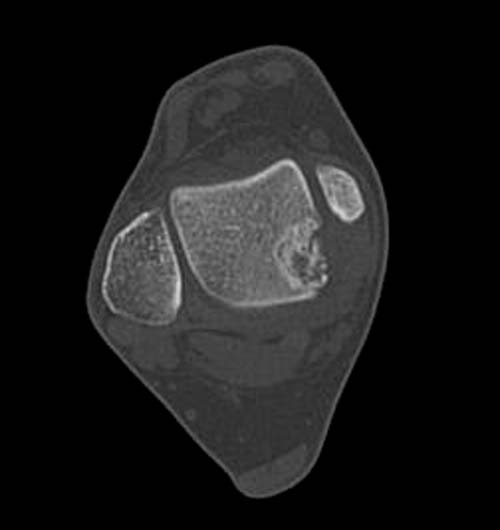

Разбираемый случай не имеет ничего общего с классическим Аваскулярным Некрозом Таранной кости. Здесь так назывемый (osteochondral defect) или osteochondritis dissecans (OCD) таранной кости, при котором патология локализуется в медиально-верхнем нагрузочном отделе. В основном OCD

на рентгенограммах не всегда заметны склерозные участки, и поэтому в большинстве диагноз устанавливается поздно. Приход КТ и МРТ улучшил диагностику, и в срезах внутри кисты можно увидеть жидкость, но это не означает проявление симптоматологии. Симптомы проявляются с момента образования внутрисуставных краевых фрагментаций!

Артроскопия с дебридментом приносит облегчение, но огромные медиально-верхние дефекты надо замещать. Хирургический доступ через медиальную лодыжку, а для замещения применяют современные алломатериалы.

Сравнивал представленные КТ с тем что есть в сети в свободном доступе - тоже не нашел разницы между OCD и AVN таранной кости

Тотальный АВН и ОСД можно отности к ишемическим заболеваниям таранной кости. Но, кроме этого, в развитии ОСД (Osteochondritis Dissecans) прямая травма хряща играет важную роль, когда наступает остеохондральный краевой

перелом. Остеохондральный перелом в зависимости от условии может быть In Situ, т.е. оставаться на месте без отрыва или быть свободным в суставе как "суставная мышь", например, как в коленном суставе.

Главное отличие - тотальное изчезновение тарана после АВН тарана, а при ОСД можно сохранить таранную кость!